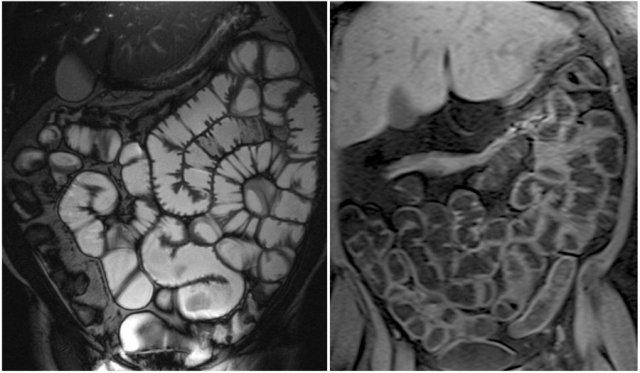

Các dấu hiệu ghi nhận được:

- Hình ảnh đảo ngược nếp gấp niêm mạc gợi ý bệnh celiac

- Lồng ruột hồi-hồi tràng (mũi tên vàng), ở bệnh nhân u lympho ruột non đa ổ (không phải tất cả các tổn thương đều được thể hiện ở đây).

- Hạch bạch huyết mạc treo to (mũi tên đỏ).